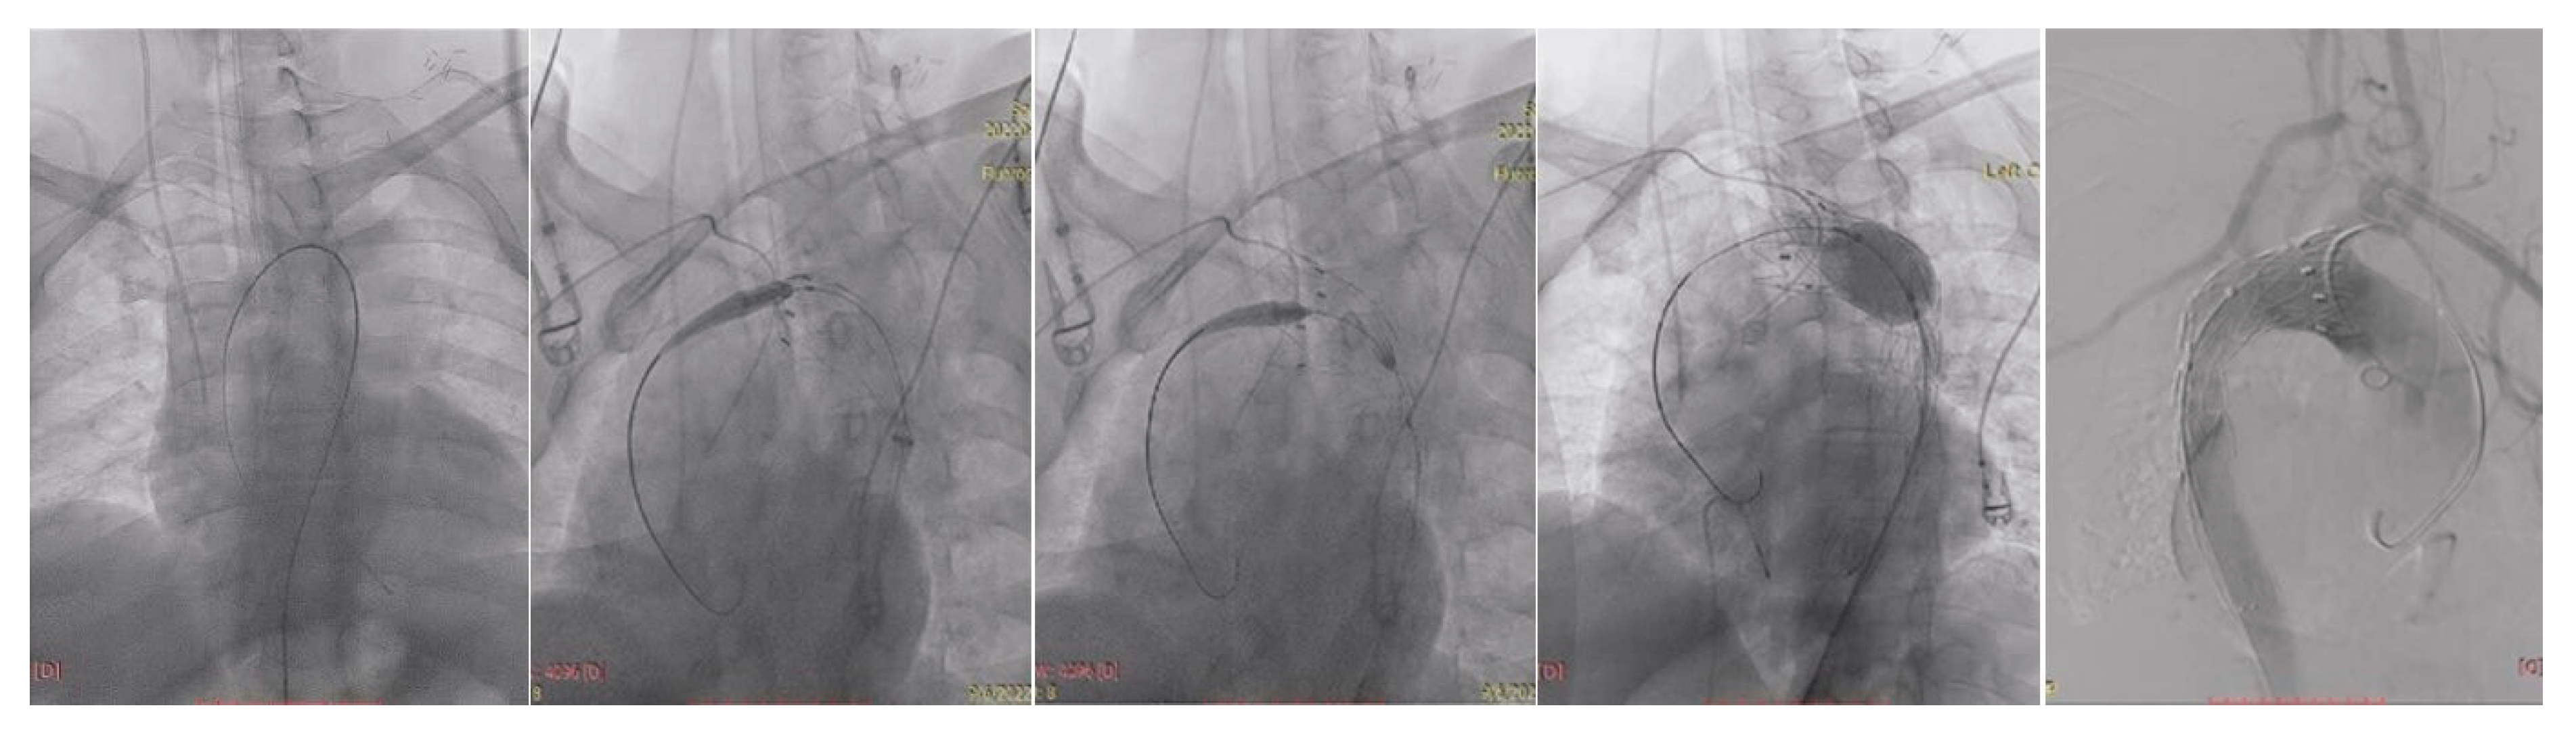

| True lumen | Severely compressed along descending thoracic and abdominal aorta | Re-expanded across thoracic segment | Stable re-expansion |

| Visceral perfusion | SMA and celiac from severely collapsed TL; R renal from FL | TL restored at visceral segment; R renal improved inflow | Full visceral patency; no endoleak |

| Procedure-related | — | No complications | No complications |